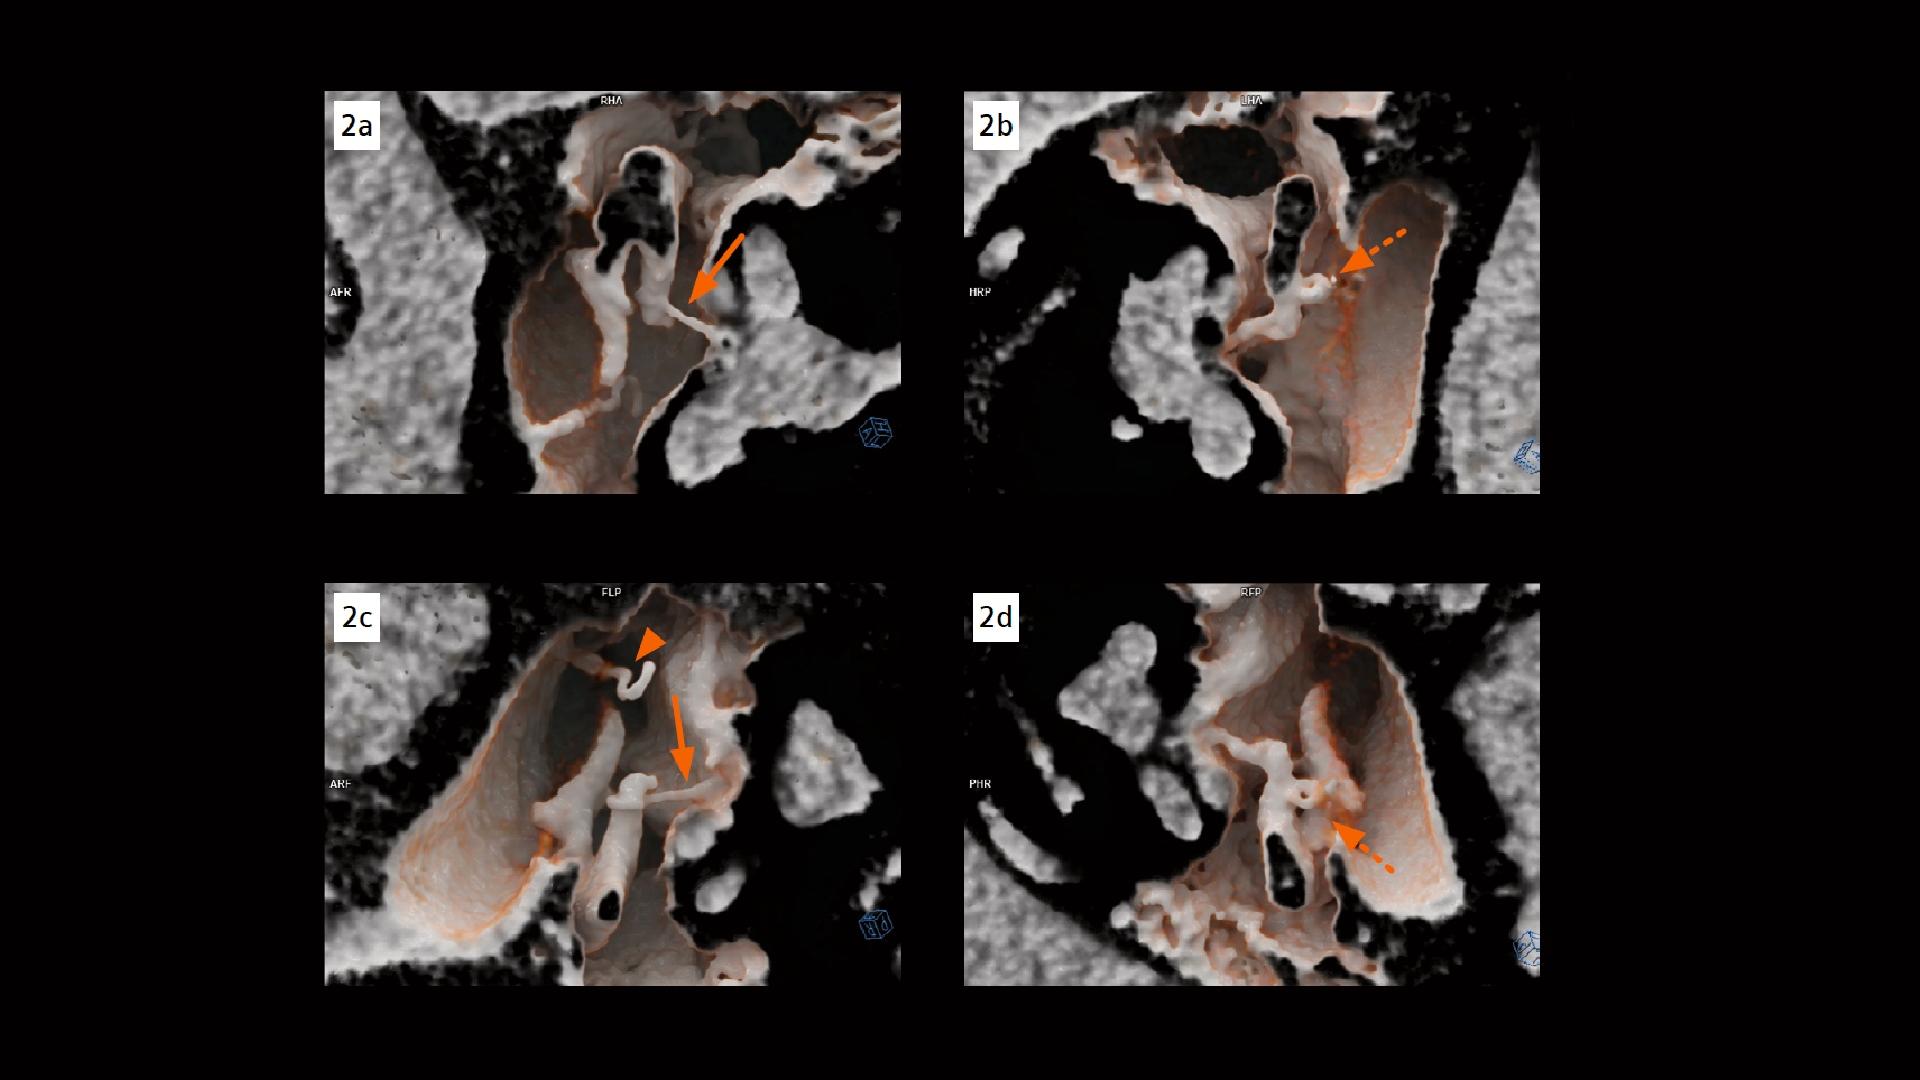

Stapes prosthesis dislocation Stapes Bone Radiology Twenty seven patients underwent ossicular reconstruction. The stapes is a bone in the middle ear that plays a crucial role in hearing. The stapes is the smallest bone of the human body. It features a link transmitting vibrations from the aerial environment of the middle ear to. The stapes is the smallest bone of the human body. The anatomy of. Stapes Bone Radiology.

Stapes prosthesis dislocation Siemens Healthineers USA Stapes Bone Radiology The stapes is a bone in the middle ear that plays a crucial role in hearing. Twenty seven patients underwent ossicular reconstruction. Progressive conductive hearing loss is the major clinical symptom of otosclerosis, which causes stapediovestibular ankylosis (fig. The stapes is the smallest bone of the human body. The stapes is the smallest bone of the human body. The anatomy. Stapes Bone Radiology.

From www.siemens-healthineers.com